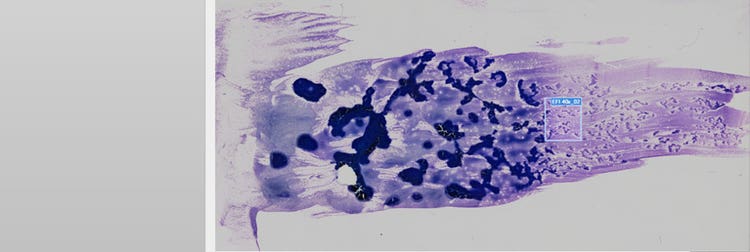

ヒト末梢血標本

図1:VS200リサーチスライドスキャナーでスキャンした急性前骨髄球性白血病(APL)を有するヒト末梢血標本。画像提供:Jana Kirsten氏、レーゲンスブルク大学医療センター、臨床化学・検査医学研究所。

このアプリケーションでは、末梢血に、分裂核または大量の顆粒を伴う腫瘍性前骨髄球が見られます(図2、オレンジ色の矢印)。これらの腫瘍性前骨髄球は、骨髄芽球だけでなく骨髄でも見られ、骨髄芽球には束状のアウエル小体が認められます(A、B、Cの緑の矢印)。APLが疑われる場合は、これらの画像を見つけることが重要です。

図2の画像A(40倍)とB(60倍)を比較すると、低倍率でもアウエル小体と顆粒が明瞭に視認できるため、NA1.4の40倍UPLXAPO油浸対物レンズの方に利点があることがわかります。また、スキャンにかかる時間は、40倍対物レンズでは60倍対物レンズの半分ほどで済みます(面積1 × 1 cmのスキャン時間:40倍 = 4:40分、60倍 = 10:30分)。